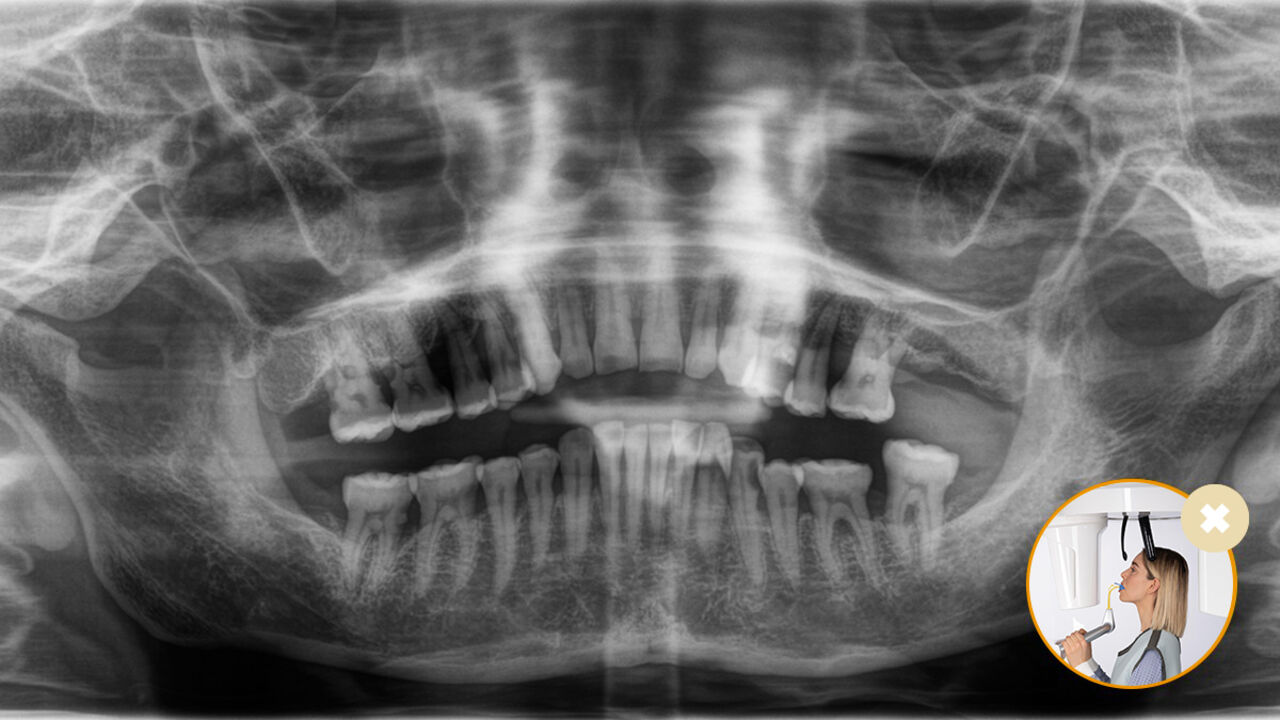

Correct patient positioning leads to high image quality to support an accurate diagnosis and facilitates and improves patient experience.

This is our 10-point concept for easy patient positioning and X-ray imaging. It is primarily about two things: high image quality and comfort for the patient and the assistant.

The Result: Precise scans thanks to the occlusal bite block